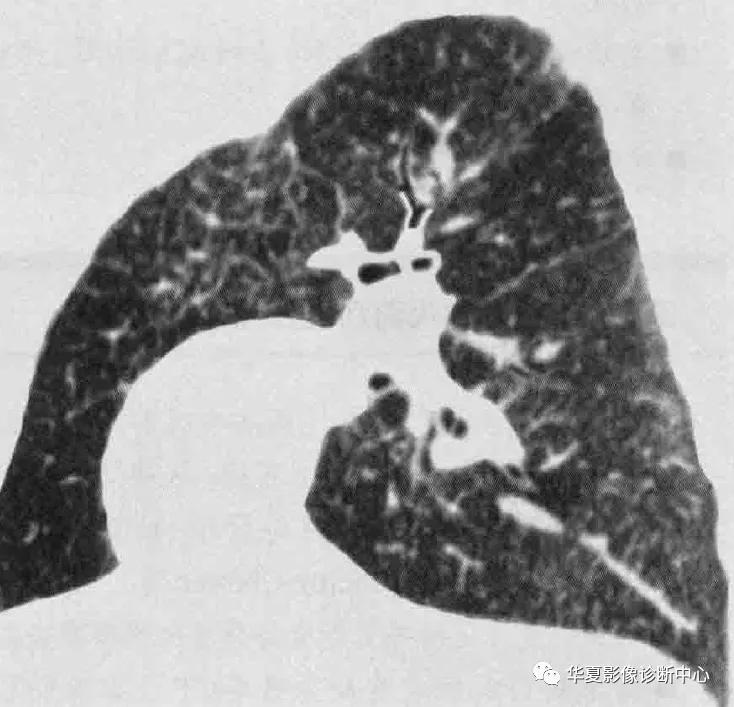

影像学表现:大多数转移性钙化患者X线表现正常,如果异常,表现包括大量直径3-10mm松散的、边界不清的结节灶,类似空腔结节或肺实质病变的斑片状病灶,主要累及上肺,钙化在X线不大明显。CT典型表现为松散的、边界不清的、直径3-10mm结节,位于小叶中心且上叶分布最多,边界可很清楚,结节钙化可是点状、分散的,或偶尔环形,钙化血管典型的可见于胸大肌和胸小肌之间,还可能出现广泛磨玻璃、斑片状实变及肺动脉和左心房壁的钙化。